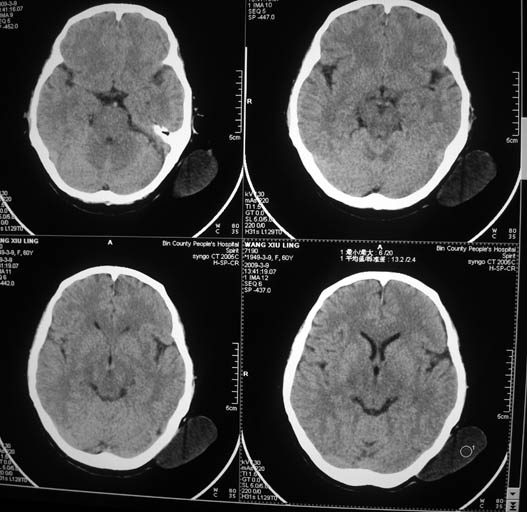

标题: CT18574:女,60岁,头部肿物。 [打印本页]

标题: CT18574:女,60岁,头部肿物。

女,60岁,头部肿物。ct值为12hu。

左枕区头皮纤维瘤可能性大。

左枕部软组织影,考虑皮样囊肿?最好穿刺!